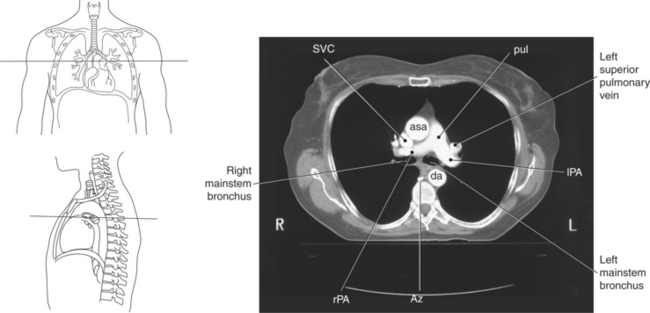

Blood travels to and from the heart through the great vessels, which include the aorta, pulmonary arteries and veins, and superior and inferior venae cavae (Figures 6.54 and 6.55). The aorta is the largest artery of the body and can be divided into the ascending aorta, aortic arch, and descending aorta. The ascending aorta begins at the base of the left ventricle at the level of the sternal angle, then curves superiorly and posteriorly as the aortic arch over the root of the left lung. The top of the aortic arch is approximately at T3 (Figures 6.56 and 6.57). The arch continues as the descending aorta posterior to the left bronchus and pulmonary trunk, on the left side of the vertebral body of T4 (Figures 6.58 and 6.59). The descending aorta passes slightly anterior and to the left of the vertebral column as it descends through the thoracic and abdominal cavities (Figure 6.60). While in the thoracic cavity, the descending aorta is commonly called the thoracic aorta, and while in the abdominal cavity, it is called the abdominal aorta. The pulmonary trunk is the origin of the right and left pulmonary arteries and lies entirely within the pericardial sac. It arises from the right ventricle and ascends in front of the ascending aorta, courses posteriorly and to the left, where it bifurcates at the level of the sternal angle (T4) into the right and left pulmonary arteries (Figures 6.61 through 6.63). The pulmonary trunk is attached to the aortic arch by a fibrous cord called the ligamentum arteriosum, the remnant of an important fetal blood vessel (ductus arteriosus) that links the pulmonary and systemic circuits during fetal development (Figures 6.54 and 6.61). The right pulmonary artery courses laterally, posterior to the ascending aorta and superior vena cava, and anterior to the esophagus and right mainstem bronchus, to the hilum of the right lung. At the root of the right lung, the right pulmonary artery divides into two branches, with the lower branch supplying the middle and inferior lobes and the upper branch supplying the superior lobe (Figures 6.61 through 6.64). The left pulmonary artery, shorter and smaller than the right, is also the most superior of the pulmonary vessels. It travels horizontally, arching over the left mainstem bronchus, and enters the hilum of the left lung just superior to the left mainstem bronchus (Figures 6.61 through 6.64). Within the lungs, each pulmonary artery descends posterolateral to the main bronchus and divides into lobar and segmental arteries, continuing to branch out and to follow along with the smallest divisions of the bronchial tree (Figures 6.61 and 6.64). Located inferior to the pulmonary arteries are the four pulmonary veins, two each (superior and inferior) extending from each lung to enter the left atrium (Figures 6.54, 6.55, 6.61, and 6.64 through 6.68). They commence in a capillary network along the walls of the alveoli, where they are continuous with the capillaries of the pulmonary arteries. The venous capillaries merge to form small vessels that unite successively to eventually form a single trunk for each lobe: three for the right and two for the left lung. Frequently the trunk from the middle lobe of the right lung unites with the trunk from the upper lobe, forming just two trunks on the right side prior to entering the left atrium. The right superior pulmonary vein collects blood from the upper lobe segments of the right lung and passes anterior and inferior to the right pulmonary artery, behind the superior vena cava. The right inferior pulmonary vein receives blood from the right lower lobes of the lung and crosses behind the right atrium to the left atrium (Figures 6.61 and 6.69 through 6.71). The left superior pulmonary vein receives blood from the left upper lobe of the left lung and courses anterior and inferior to the left main bronchus as it enters the left atrium. The left inferior pulmonary vein drains the inferior lobe of the left lung and passes toward the left atrium anterior to the bronchi (Figures 6.61 and 6.72 through 6.74). The pulmonary veins course more horizontally than the pulmonary arteries and are ultimately oriented toward the left atrium. At the root of the lungs, the pulmonary veins are anterior to the pulmonary arteries, which are anterior to the bronchus. While within the lungs, the branches of the pulmonary arteries are anterior to the bronchi, which are anterior to the pulmonary veins. The superior and inferior venae cavae are the largest veins of the body. The superior vena cava is formed by the junction of the brachiocephalic veins, posterior to the right first costal cartilage, and carries blood from the thorax, upper limbs, head, and neck (Figure 6.24). As it travels inferiorly, it is located posterior and lateral to the ascending aorta before entering the upper portion of the right atrium (Figures 6.54 through 6.59). The inferior vena cava is formed by the junction of the common iliac veins in the pelvis and ascends the abdomen to the right of the abdominal aorta and anterior to the vertebral column. It passes through the caval hiatus of the diaphragm and almost immediately enters the inferior portion of the right atrium (Figures 6.75 and 6.76).

Figure 6.59 Axial CT scan of chest with ascending and descending aorta.

Key: SVC, Superior vena cava; asa, ascending aorta; da, descending aorta; ca, carina;

Figure 6.63 Axial CT scan of chest with pulmonary trunk.

Key: SVC, Superior vena cava; pul, pulmonary trunk; asa, ascending aorta; da, descending aorta; rPA, right pulmonary artery; Az, azygous vein; lPA, left pulmonary artery.